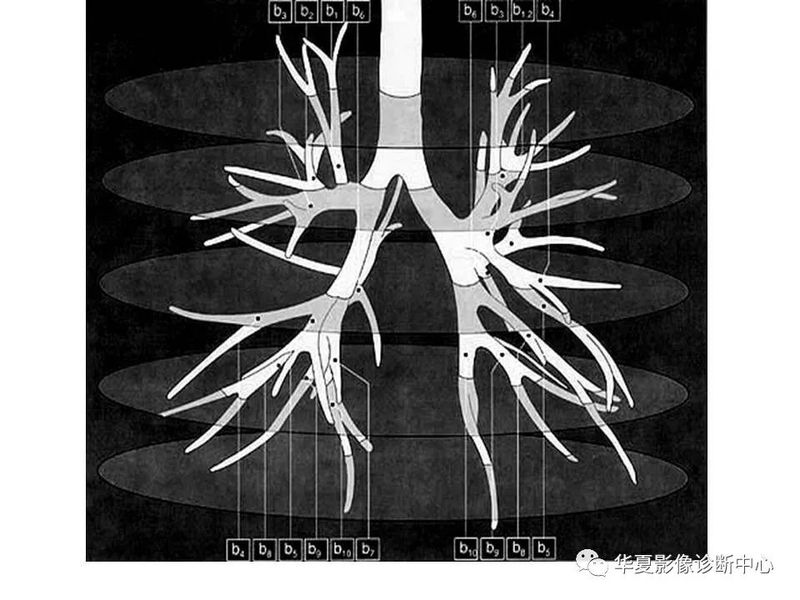

干货 | 汇总胸部CT读片扫盲知识,看懂胸部CT不再难